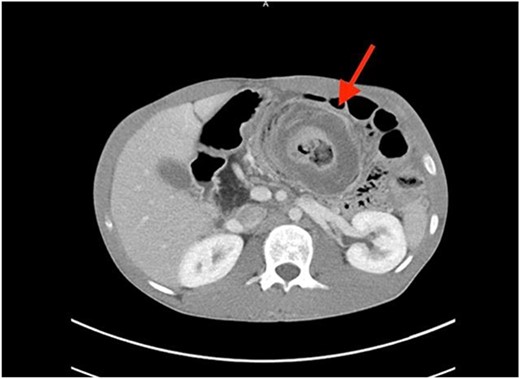

A coronal computed tomography (CT) scan with contrast showed a massive, small bowel to large bowel intussusception involving the majority of the ascending colon and portions of the cecum (Fig. 1). In addition, an axial CT scan showed the classic target sign associated with intussusception (Fig. 2). Due to the patient’s age, a pathologic lead point was suspected, hence surgery was consulted.

Axial CT scan showing characteristic target sign of bowel intussusception.

In cases of suspected intussusception, the initial diagnostic approach should involve an abdominal ultrasound examination. This method is known for its ability to reveal the characteristic bulls-eye or target appearance, although its accuracy is reduced in adults [2, 6]. Even if the ultrasound results are positive or inconclusive, a CT scan should follow, serving as the most accurate diagnostic test for adult intussusception. In adults, the CT scan typically also depicts the bulls-eye or target appearance, as seen in Fig. 2 [2].